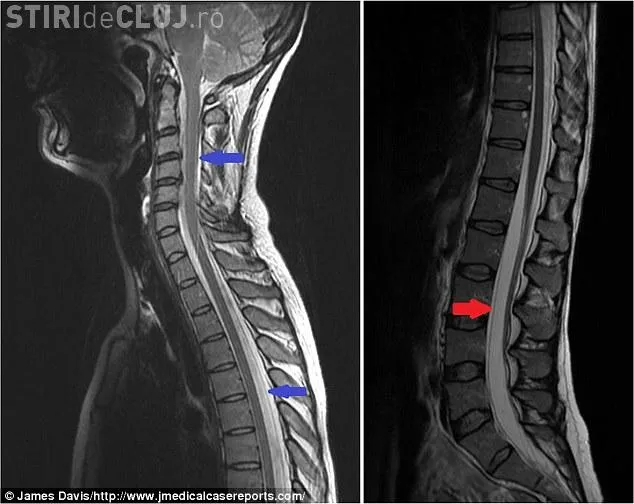

După ce i-au făcut un computer tomograf, medicii au stabilit că lichidul care se află în jurul creierului și a coloanei se scurgea printr-o ruptură musculară.